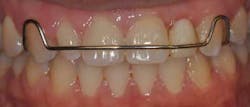

In order to establish anterior group function on substituted teeth, a clinician must critically evaluate the overbite and overjet of each tooth and anticipate any additions or subtractions to the functional surfaces that might be needed. When the orthodontist places the brackets to esthetically align the gingival margins, the substituted cuspid and bicuspid will end up in supra- and infra-occlusion, respectively. Once the ideal position of the gingival framework is properly established, the shapes of the teeth must be adjusted to mimic the replaced tooth. The dimensions of the bicuspid will need to be increased mesio-distally and inciso-gingivally, and the lingual cusp will need to be reduced. The cuspid, on the other hand, will need reduction in the incisal-gingival and mesial-distal dimensions, flattening of the labial surface, and a steepening of the lingual convexity. In order to avoid excessive enamel removal and an increase in color saturation, it is best to perform canine substitution in patients who have teeth of similar overall dimensions to those that they are replacing. Almost all substitution cases will also require additive recontouring of teeth in the form of bonding or veneers with the preferred long-term restoration being the veneer. If an excessive addition or reduction is anticipated, a full-coverage restoration may be necessary and the clinician might want to discuss an alternative treatment approach with the patient, such as opening space and preparing for prosthetic replacement.

contours and positioning were achieved. B: M/D dimensions a bit

excessive and gingival margin positioned to apical. C: Significant

cervical bulge and discoloration evident after recontouring.